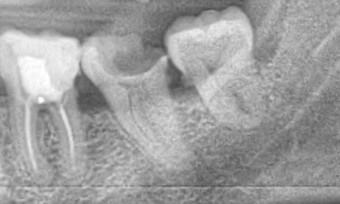

Caries avanzada, muy

cerca del tejido pulpar.

Evitando una endodoncia

con el uso de CARIESEND

Después del cepillado y enjuague bucal de rutina, se puede aplicar el gel Cariesend, sobre la encia inflamada con un algodón y se deja actuar por 5 minutos antes de enjuagar. El gel Cariesend actúa con el poder de varias sustancias de origen natural como: papaína, tapsina, flavonoides, taninos y catequinas. Estos tienen acción comprobada en numerosos estudios como bactericida, antimicótica, antivírica, antiinflamatorio, desinfectante y cicatrizante. Tan pronto como pueda debe visitar al odontólogo, para determinar las causas y el tratamiento del problema periodontal. Con un estudio radiográfico el especialista determina si hay daño oseo y le indicará el tratamiento a seguir.